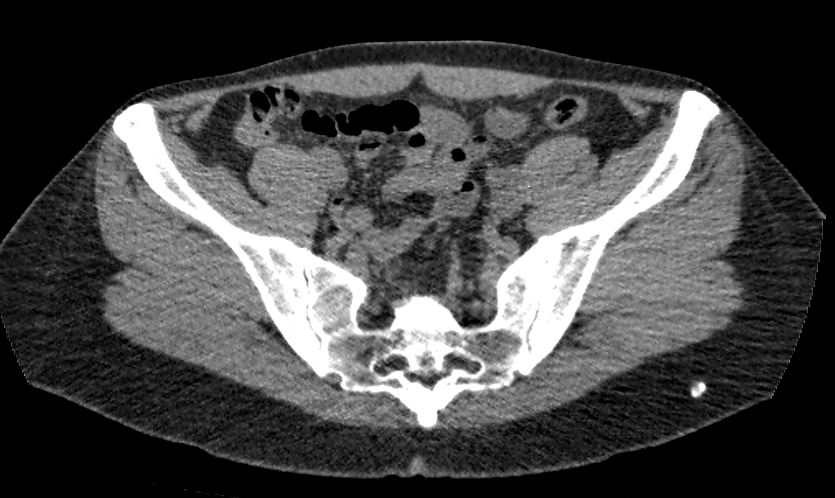

Методика КТ позволяет оценить анатомическое строение почек, надпочечников, состояние мочеточников и мочевого пузыря, кроме того, дает возможность визуализировать сосудистую систему и регионарные лимфатические узлы.

Сканирование применяется для выявления воспалительных заболеваний почек, чашечно-лоханочной системы, мочеточников и мочевого пузыря, также позволяет обнаружить конкременты на фоне мочекаменной болезни, диагностировать доброкачественные и злокачественные новообразования, точно классифицировать кистозные образования по системе Bosniak, что особенно важно для урологов и нефрологов, а также определить степень поражения регионарных лимфатических узлов. Кроме того, КТ используется для диагностики травматических повреждений органов мочевыделения, аномалий развития почечно-лоханочной системы, дает максимальную информацию для хирурга при планировании оперативного вмешательства.

Что показывает КТ почек, мочеточников, мочевого пузыря

- опущение почек;

- аномалии развития почек, мочетоников

- доброкачественные и злокачественные новообразования;

- камни (конкременты);

- уретероцеле

- сосудистую патологию (сосудисто-мочеточниковый конфликт, инфаркт почки);

- последствия оперативных вмешательств;

- увеличение лимфоузлов в брюшной полости, забрюшинном пространстве и малом тазу;

- травматические изменения

- патологии сосудов малого таза.